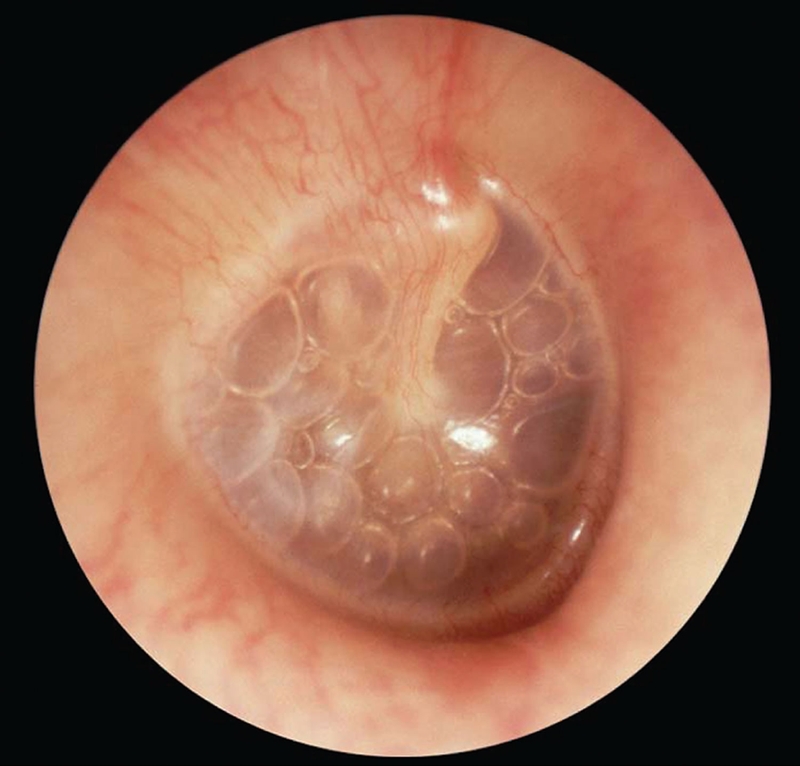

• Viêm tai giữa tụ dịch: Đôi khi xảy ra sau khi nhiễm trùng tai đã diễn ra và dịch vẫn bị tụ lại phía sau màng nhĩ. Trẻ bị viêm tai giữa tụ dịch có thể không có triệu chứng, nhưng bác sĩ sẽ có thể nhìn thấy dịch phía sau màng nhĩ bằng một dụng cụ khám tai đặc biệt.

Tại sao nhiễm trùng tai ở trẻ em hay gặp hơn người lớn? 2

Hình ảnh viêm tai giữa tụ dịch